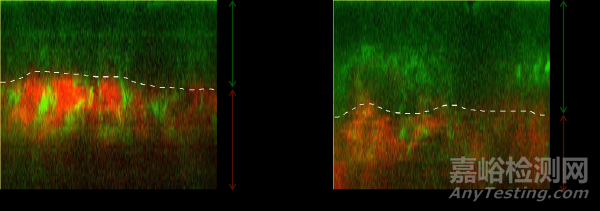

圖8. b) 使用產(chǎn)品28天后,上表層逐漸增厚(虛線為真表皮交界處)

圖12. 監(jiān)測(cè)表皮層厚度變化

注:隨回訪周期變化:使用產(chǎn)品28天后,上表皮厚度顯著改善8.45%;0μm處為角質(zhì)層表面;0~40μm處為表皮層;50~60μm處(圖示虛線處)為真表皮交界處,紅色膠原纖維出現(xiàn)處,可認(rèn)為是真皮最淺,綠色細(xì)胞結(jié)構(gòu)消失處,可認(rèn)為是表皮最深;60~120μm處為真皮淺層,紅色信號(hào)為膠原纖維,綠色信號(hào)為彈性纖維。